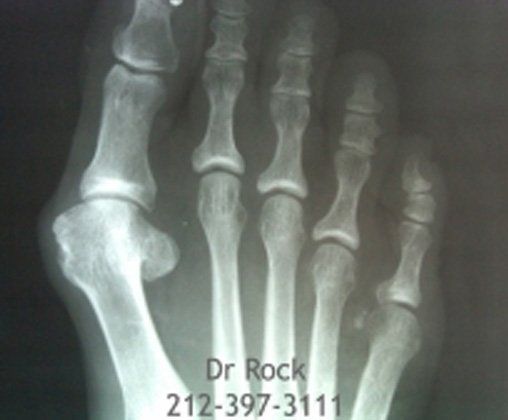

Take a look at our x-ray pictures of our recent footwork and see how your feet can benefit.

Whether you want to improve the look of your feet or need to relieve pain,

you can find out the best option for you with our FREE phone consultation.